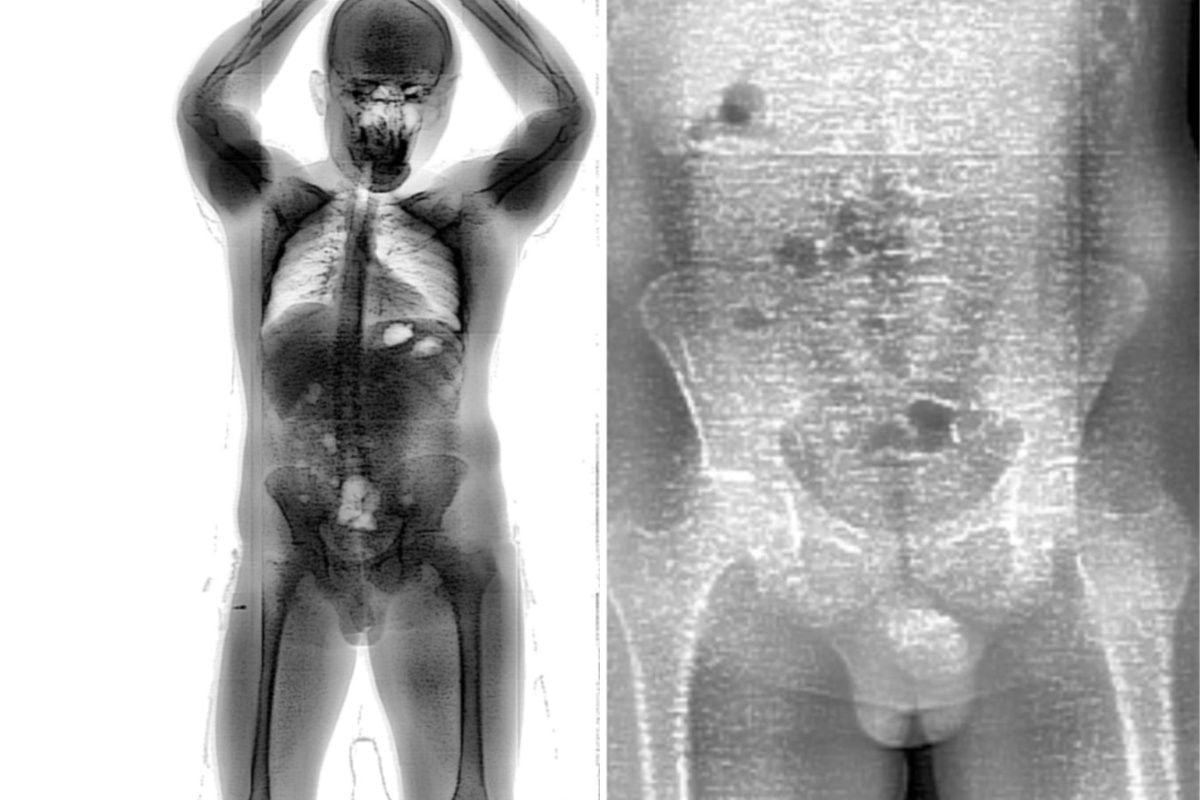

Graças à tecnologia do BodyScan e à atuação rápida dos policiais penais, o plano foi frustrado. Durante o procedimento padrão de triagem, o scanner corporal apontou alterações na região intestinal do homem, o que levou à realização de uma entrevista com a equipe de segurança.

Na conversa, o custodiado confessou ter engolido os invólucros e revelou que adquiriu a droga com uma mulher não identificada ainda na carceragem de Guanambi. Segundo ele, a decisão foi motivada pela informação de que, no Conjunto Penal de Brumado, o acesso a entorpecentes seria inviável devido à rigorosa fiscalização. Dependente químico, o interno alegou que essa seria a única forma de manter o vício.